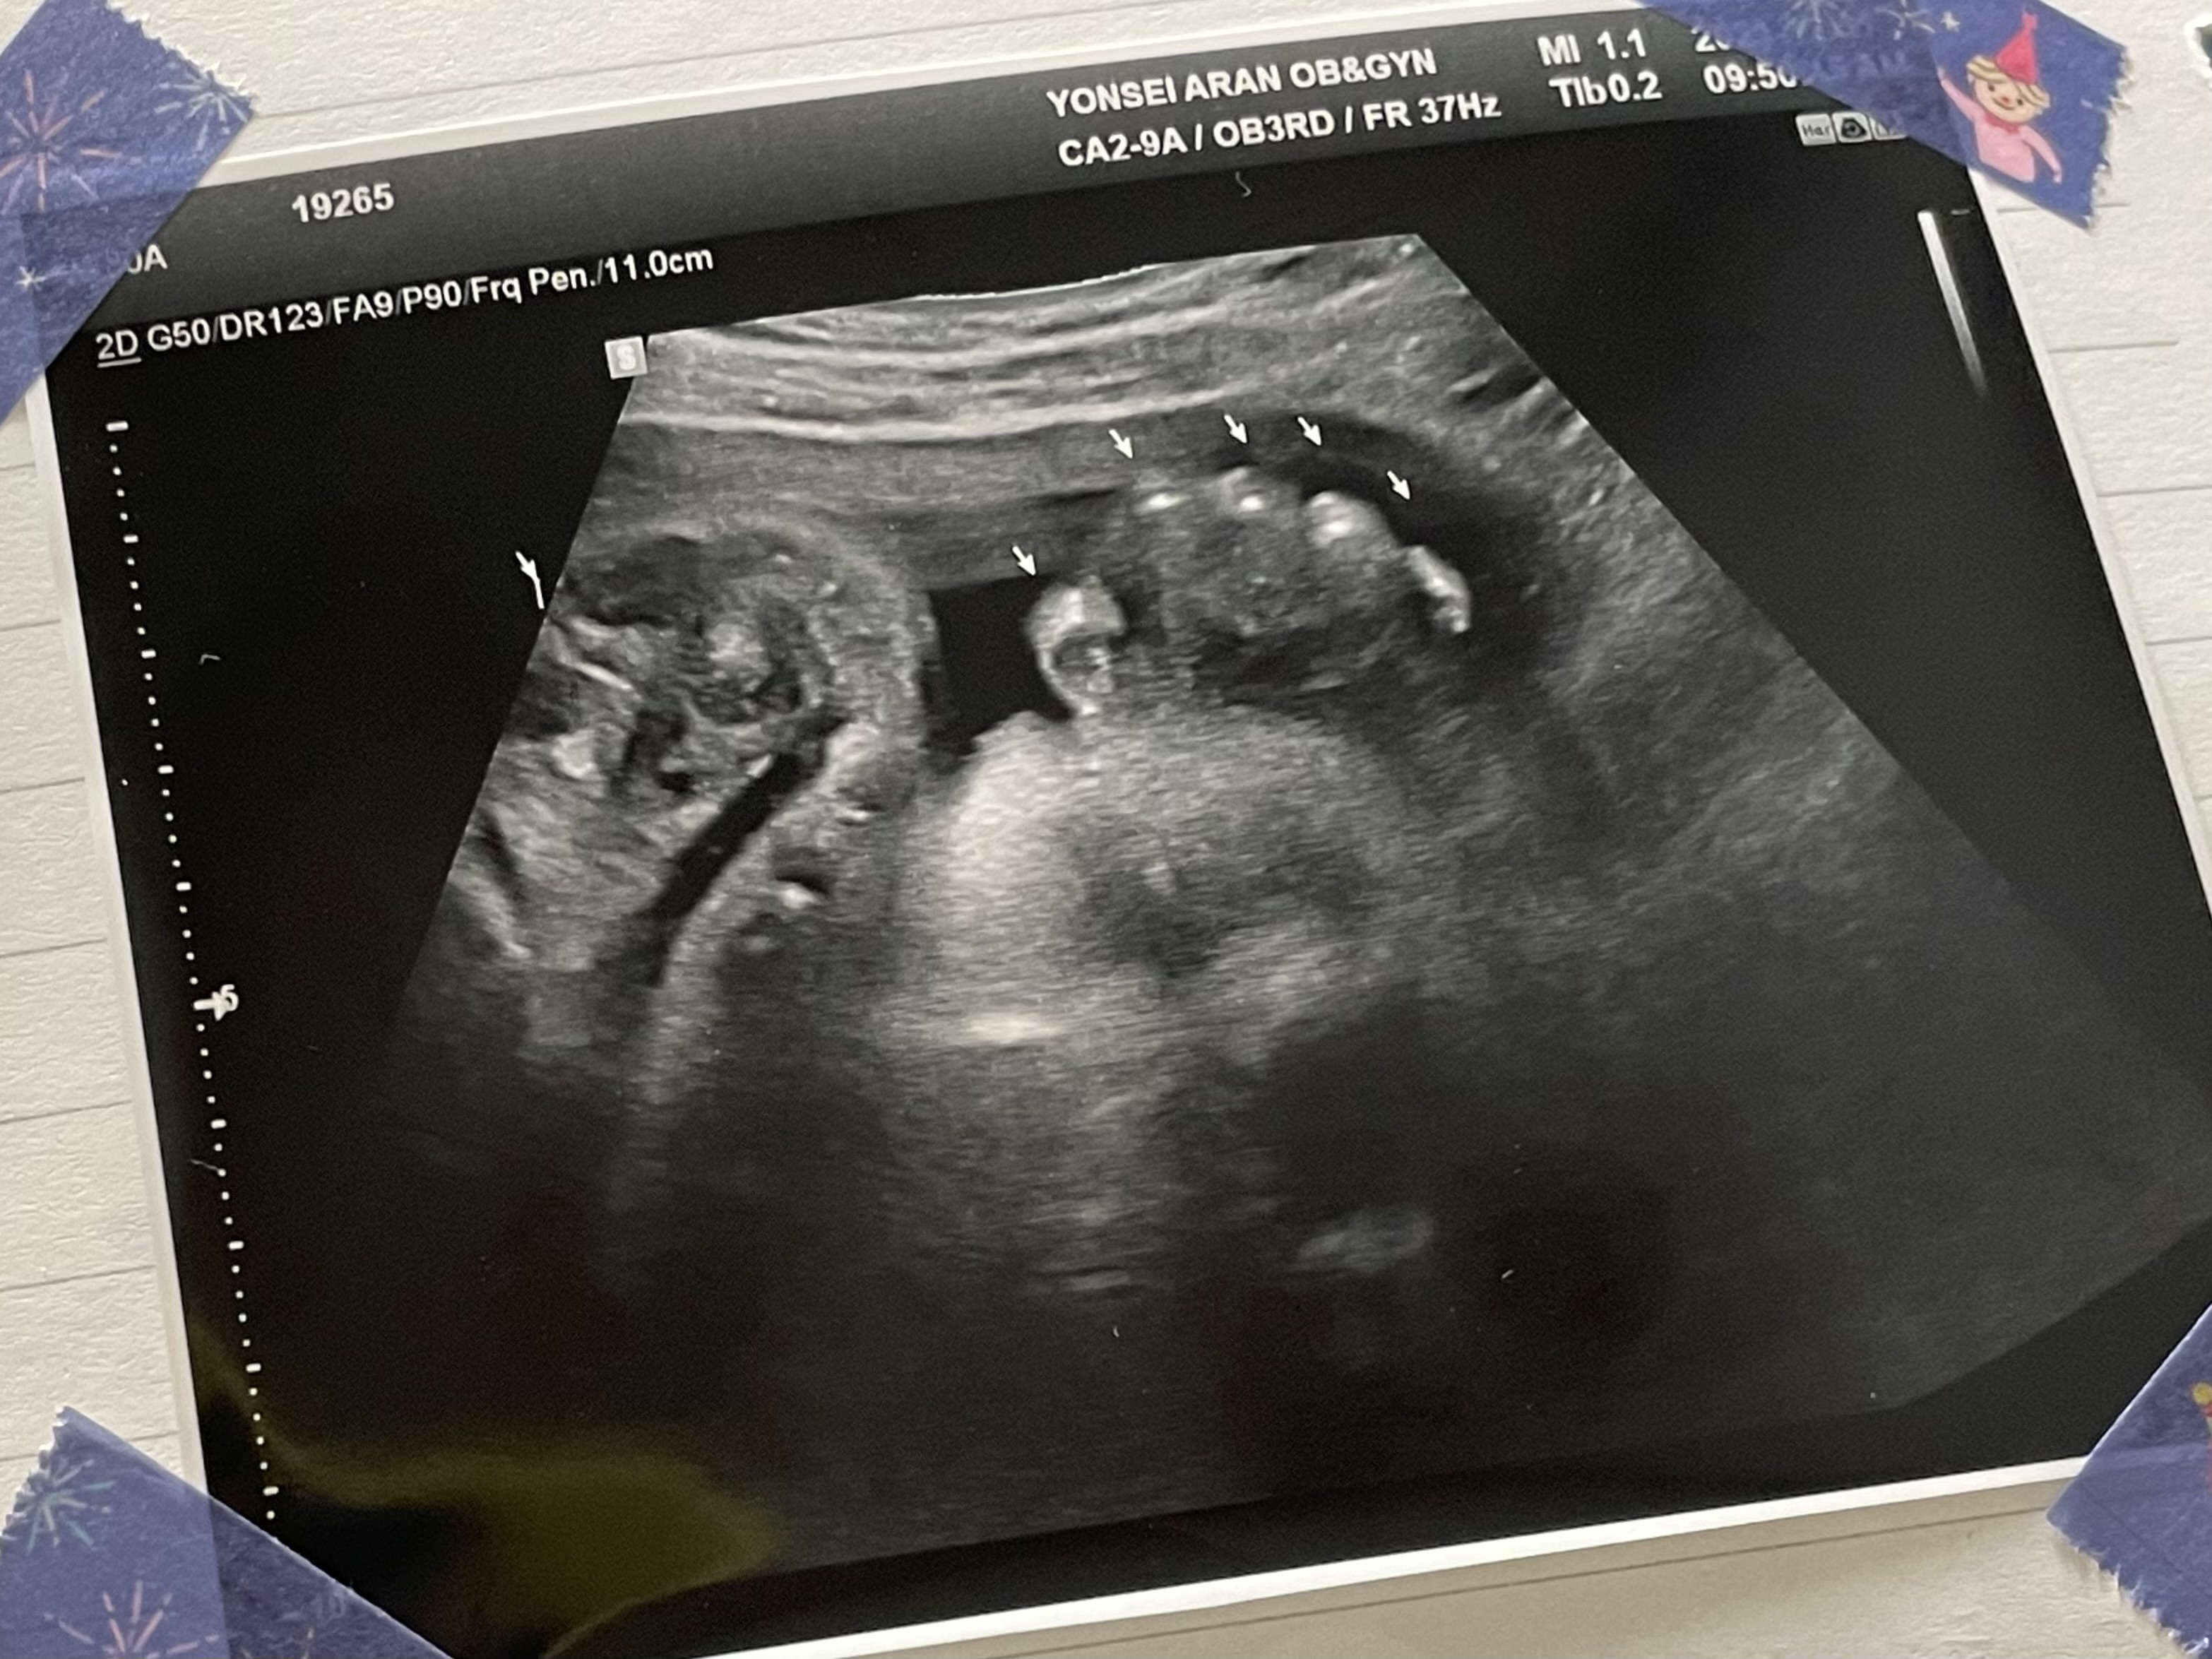

애기가 얼굴이 너무 잘보인다며 웃으셨다.

하나도 안내려왔다고...ㅠ

그와중에 머리는 역시 커졌고,